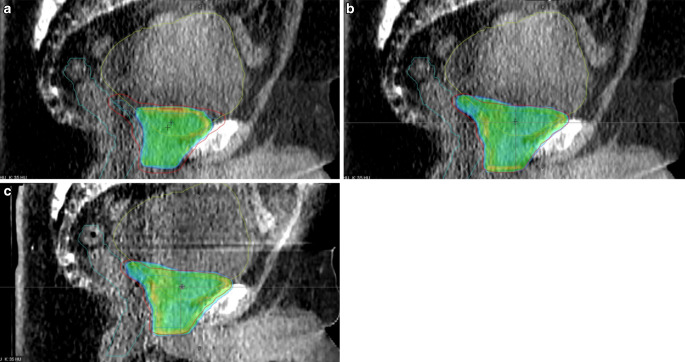

Methods: A total of 198 fractions of radiotherapy of the prostate bed (6 patients) were treated using oART with the Ethos accelerator (Varian Medical Systems, Palo Alto, CA, USA). For each fraction, volumes and several dose-volume parameters of target volumes and organs at risk were recorded for the scheduled plan (initial plan, recalculated based on daily cone beam computed tomography [CBCT]), the adapted plan, and the verification plan, which is the dose distribution of the applied plan recalculated on the closing CBCT after the adaptation process. Clinical acceptability for all plans was determined using given dose-volume parameters of target volumes. Additionally, the time needed for the adaptation process was registered and compared to the time required for the daily treatment of five conventional IGRT patients.

Results: Volumes of target and organs at risk (OAR) exhibited broad variation from day to day. The differences in dose coverage D98% of the clinical target volume (CTV) were significant through adaptation (p < 0.0001; median D98% 97.1-98.0%) and further after verification CBCT (p < 0.001; median D98% 98.1%). Similarly, differences in D98% of the planning target volume (PTV) were significant with adaptation (p < 0.0001; median D98% 91.8-96.5%) and after verification CBCT (p < 0.001; median D98% 96.4%) with decreasing interquartile ranges (IQR). Dose to OAR varied extensively and did not show a consistent benefit from oART but decreased in IQR. Clinical acceptability increased significantly from 19.2% for scheduled plans to 76.8% for adapted plans and decreased to 70.7% for verification plans. The scheduled plan was never chosen for treatment. The median time needed for oART was 25 min compared to 8 min for IGRT.

Abstract Image